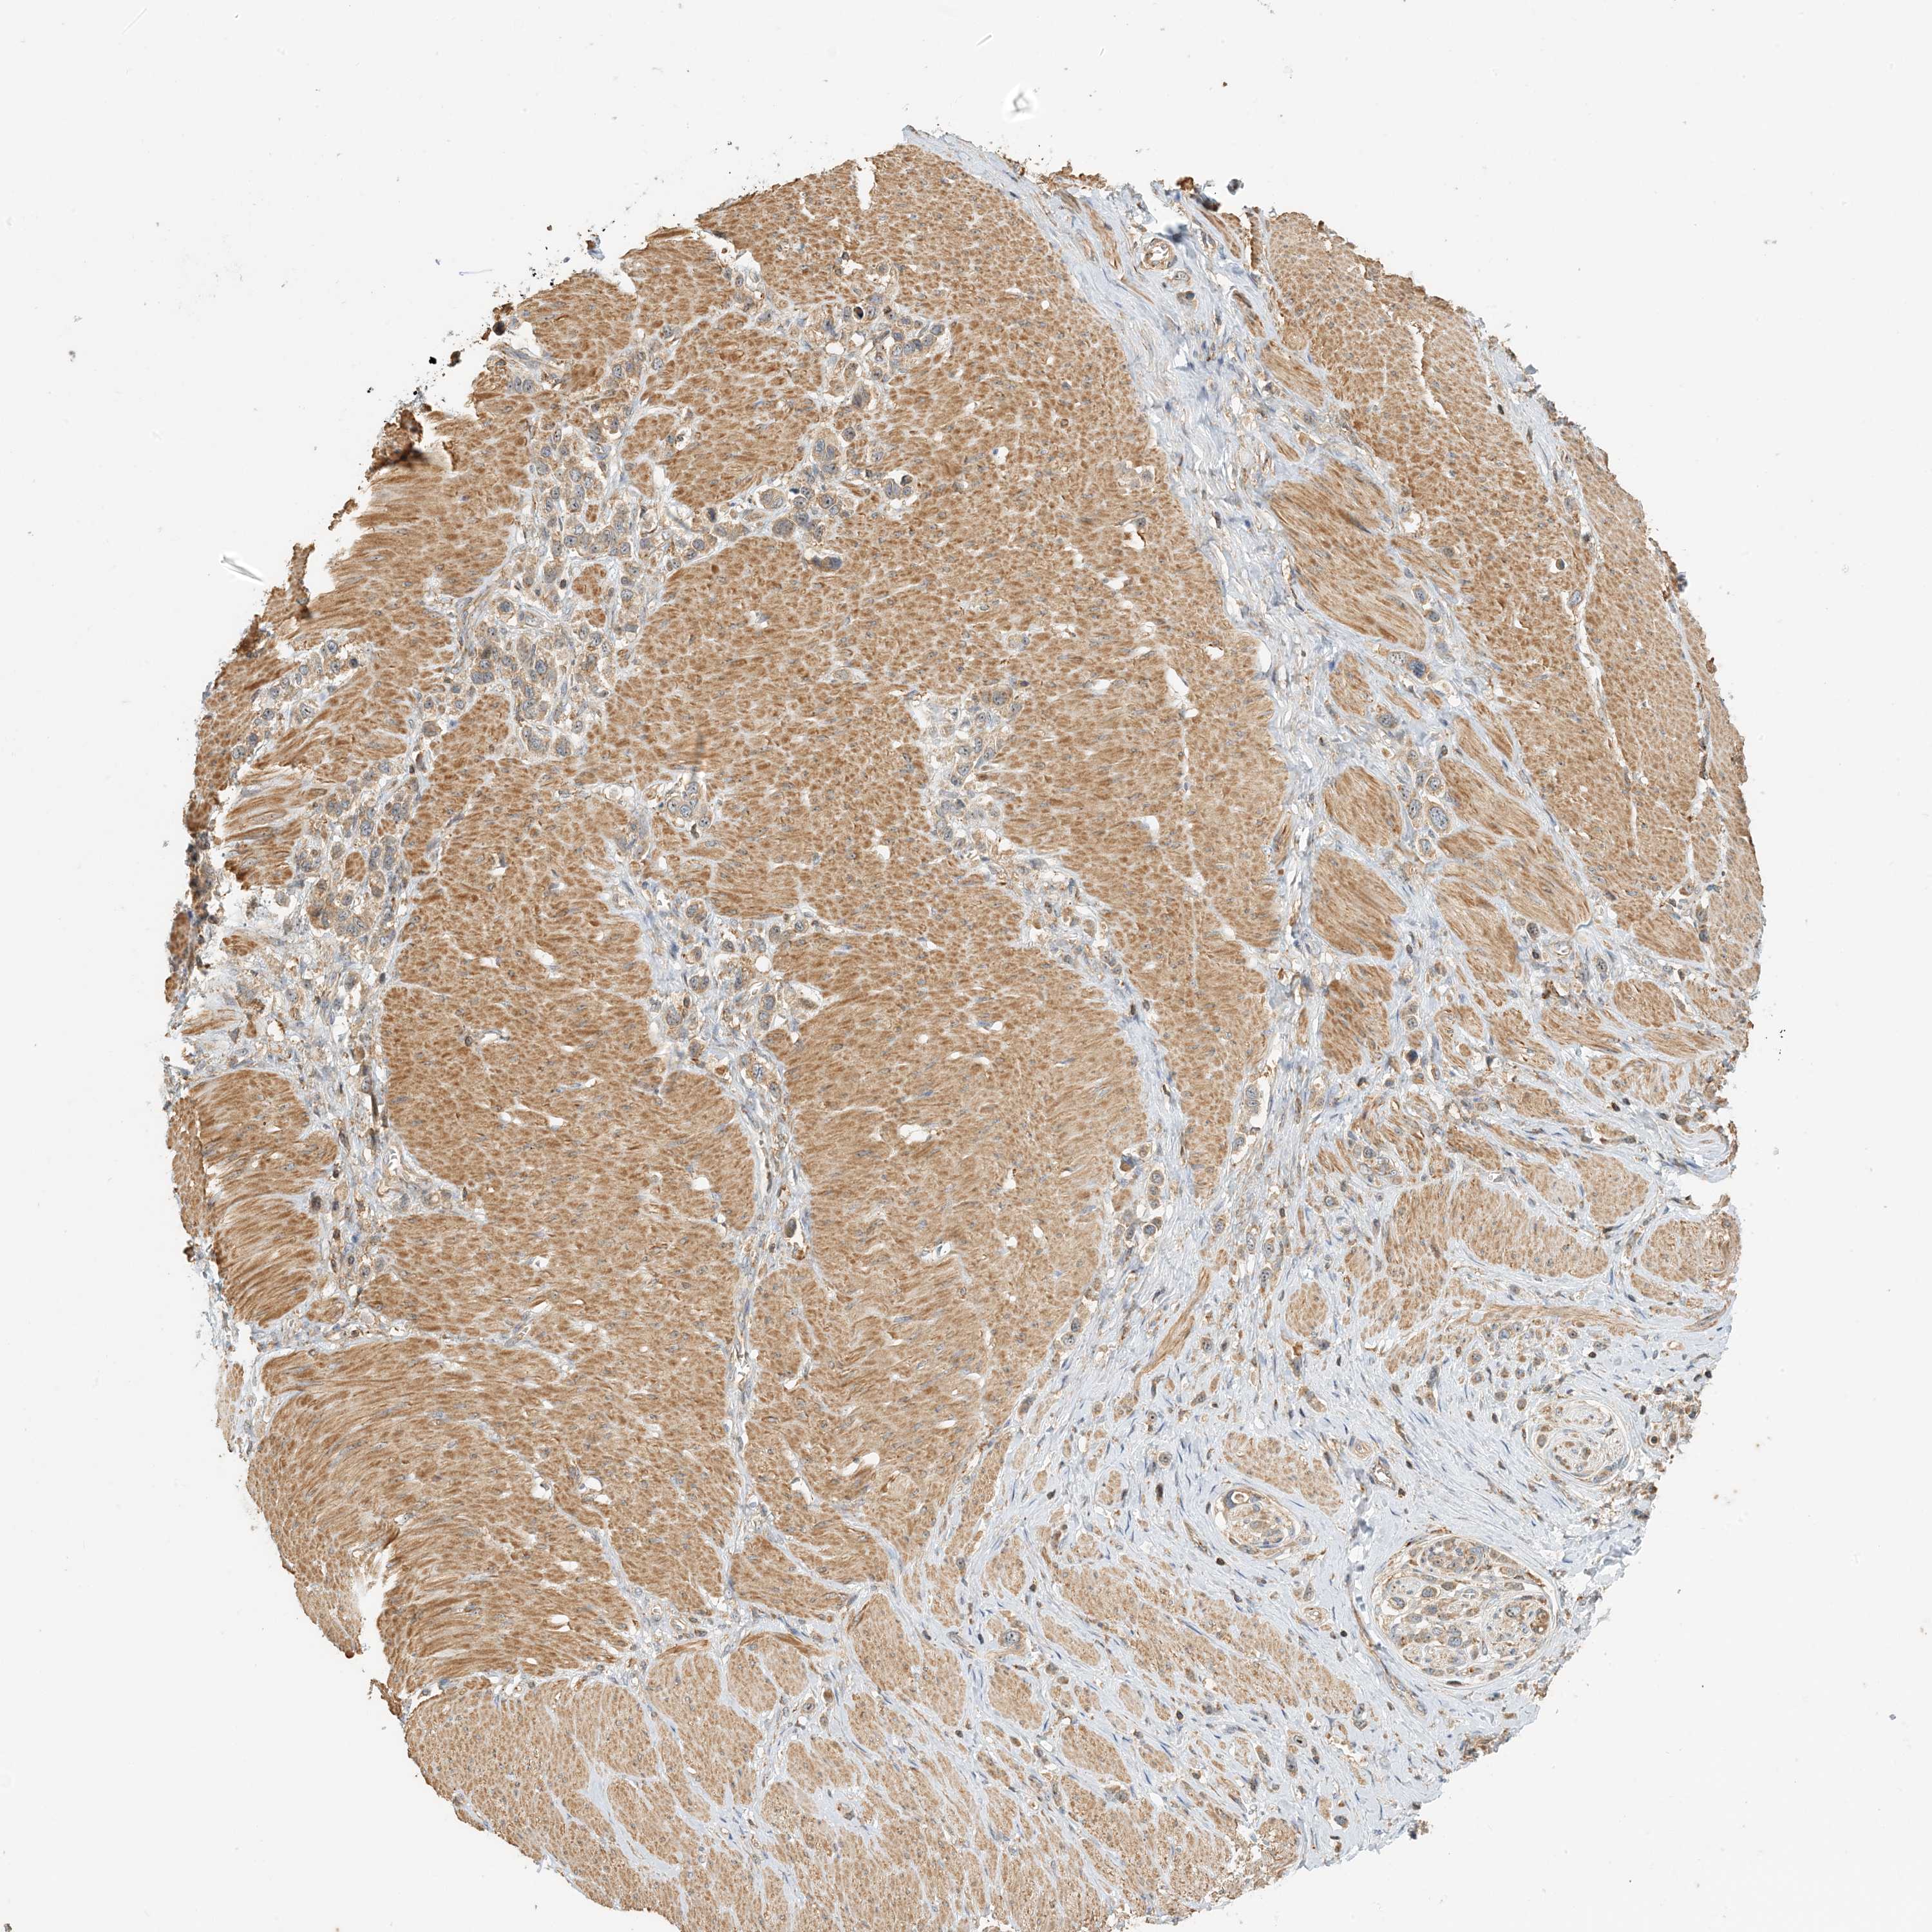

STOMACH CANCER - Protein expressioni

A mouse-over function shows sample information and annotation data. Click on an image to view it in a full screen mode. Samples can be filtered based on level of antibody staining by selecting one or several of the following categories: high, medium, low and not detected. The assay and annotation is described here.

Antibody stainingi

Antibody staining in the annotated cell types in the current human tissue is reported as not detected, low, medium, or high, based on conventional immunohistochemistry profiling in selected tissues. This score is based on the combination of the staining intensity and fraction of stained cells.

Each image is clickable and will lead to virtual microscopy that enables deeper exploration of all samples and also displays staining intensity scores, fraction scores and subcellular localization as well as patient and tissue information for each sample.

Antibody HPA035241

Staining

High

Medium

Low

Not detected

Intensity

Strong

Moderate

Weak

Negative

Quantity

>75%

75%-25%

<25%

None

Location

Nuclear

Cytoplasmic/membranous

Cytoplasmic/membranous,nuclear

Adenocarcinoma, NOS